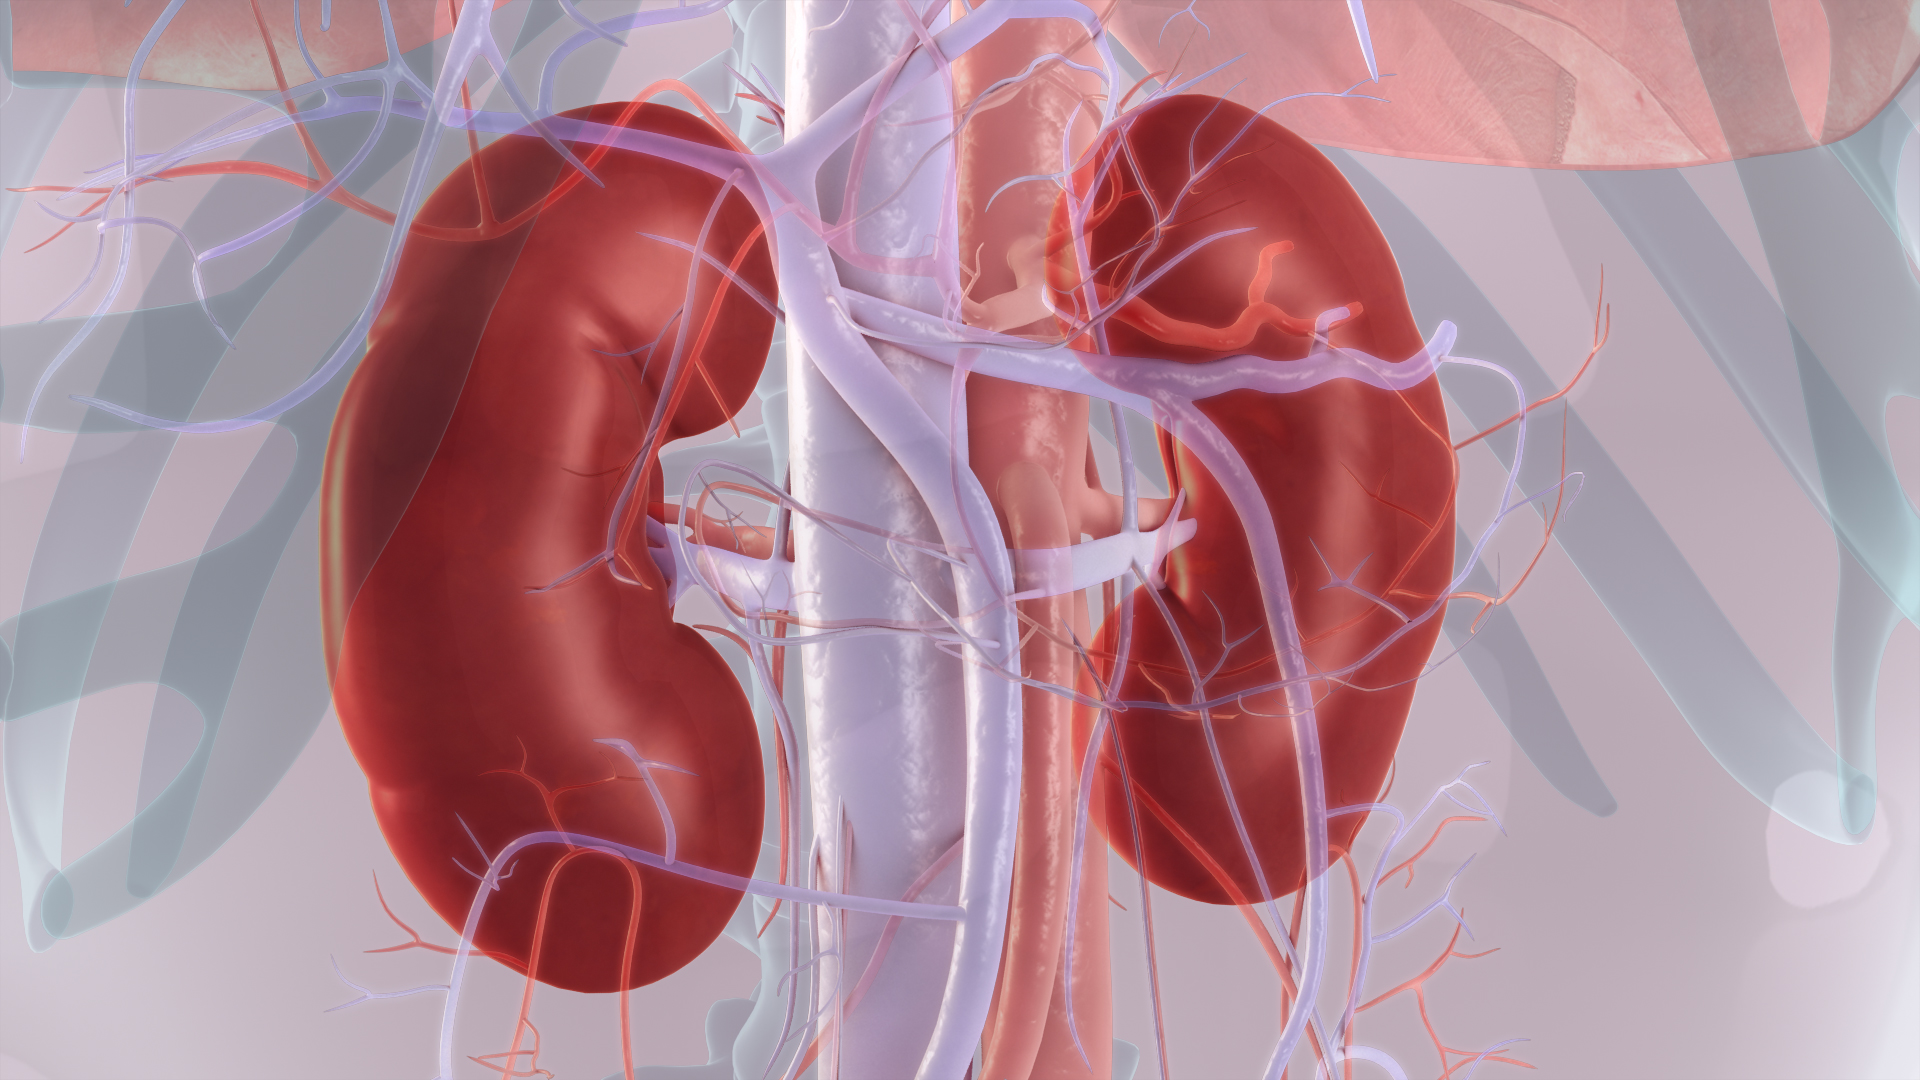

Строение почек человека: Фото и описание